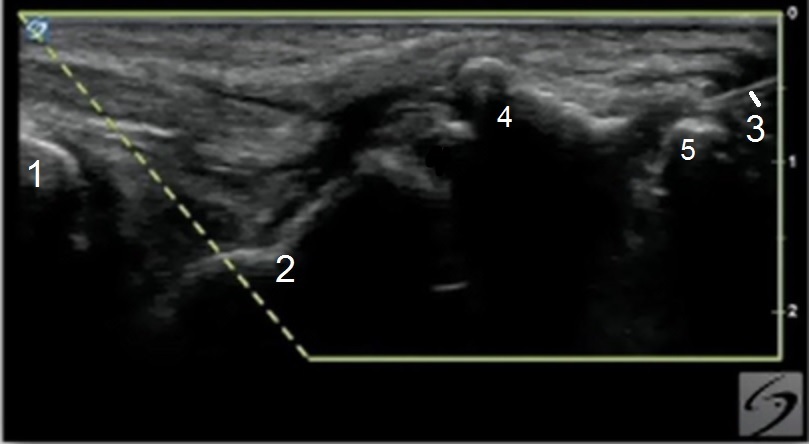

手首の第1CMC関節注射面内の画像

橈骨

舟状骨

針